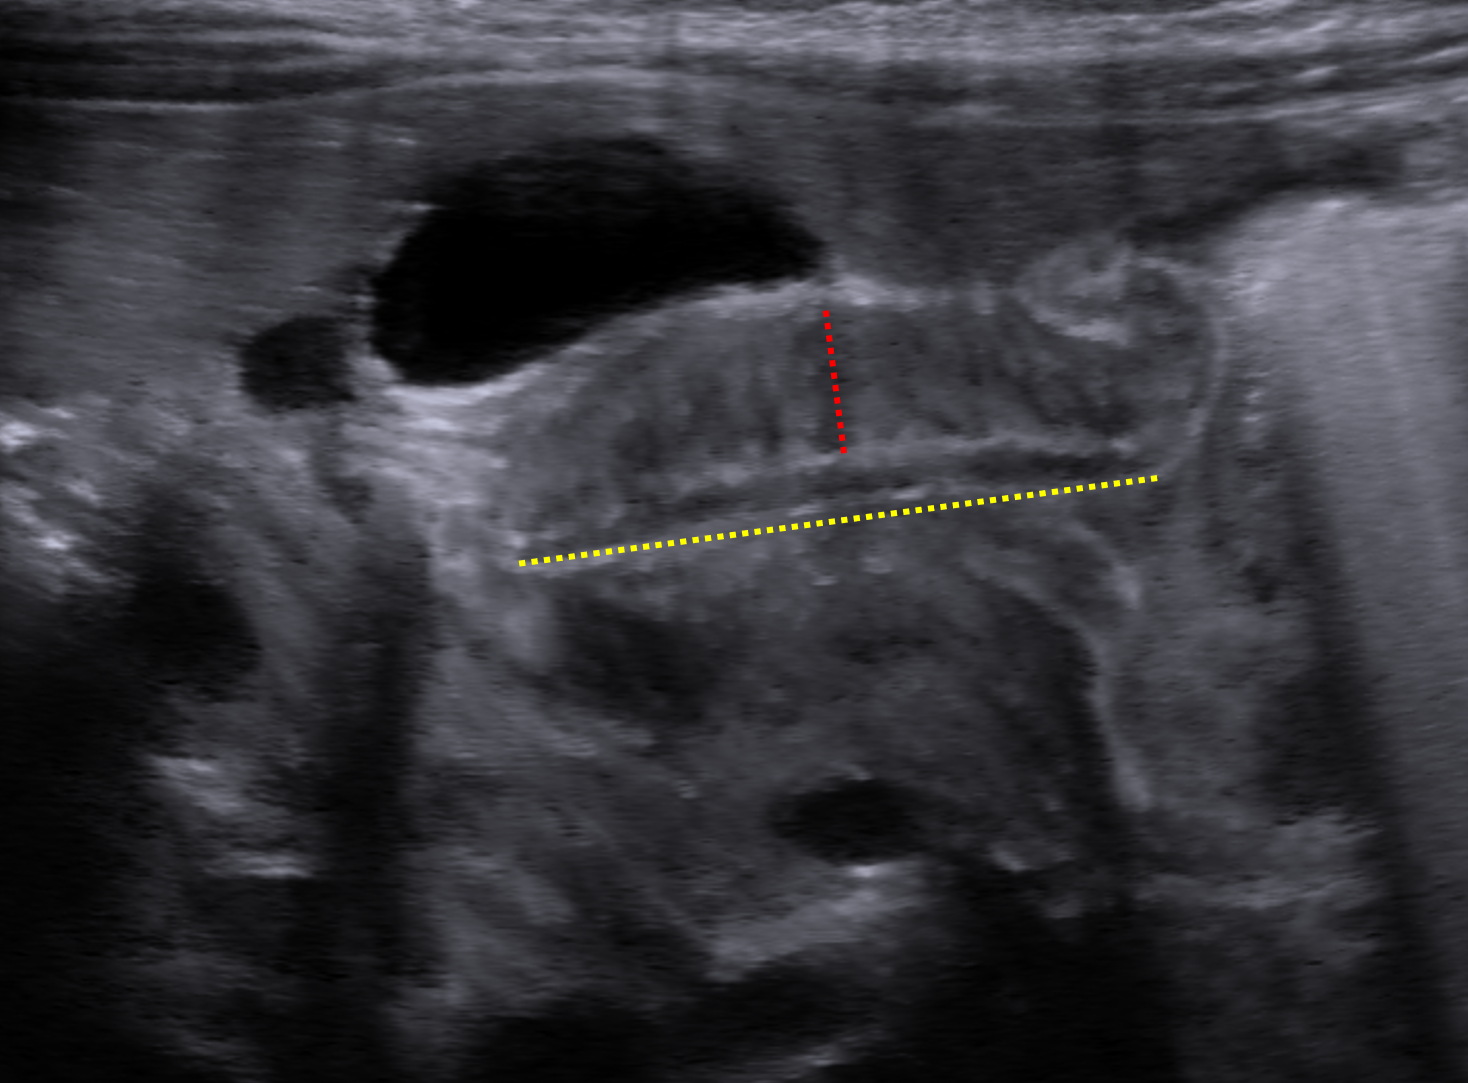

Age: 6 weeks (born at 40 weeks)

Sex: Male

Indication: Projectile vomiting

Hypertrophic pyloric stenosis

Sample ReportElongated pyloric channel with increased pyloric wall thickness and no observed bulk fluid transit from the stomach to the duodenum over 30 minutes of intermittent imaging. These findings are consistent with hypertrophic pyloric stenosis.